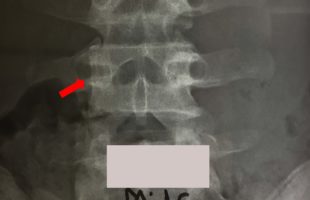

Η Μα. Φο. 26 ετών προ δεκαετίας υποβλήθηκε (αλλαχού) σε χειρουργική επέμβαση στη θωρακο-οσφυική περιοχή της σπονδυλικής στήλης (Σ.Σ.). Η επέμβαση εγένετο προκειμένου να αφαιρεθεί καλοήθης νεοπλασματική εξεργασία (επενδύμωμα) η οποία της είχε προκαλέσει σφιγκτηριακές και νευρολογικές διαταραχές στα κάτω άκρα. Προκειμένου να γίνει εξαίρεση της νεοπλασματικής βλάβης, πραγματοποιήθηκε ευρεία αφαίρεση οπίσθιων στηρικτικών στοιχείων τωνRead more →